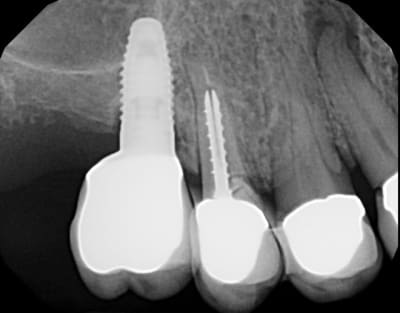

Patiente adressée pour évaluation :

son dentiste ne sait que faire.

À l'examen :

13 : belle fistule vestibulaire, mobilité, carie cervicale

14 : mobilité +++

15 : fracture racine (?), carie cervicale

Les implants datent de 5-6 ans (par un autre CD, la patiente a depuis déménagée).

Le bas , pas touche cette année, on verra en 2012.

Votre plan de tx ?

flicflac

08/04/2011 à 05h57

je le réfère à Céramik, il pose des implants...

Panorex avec Vitallium en bouche ok... au moins on sait que la patiente possède un partiel...

mobilité dent 14 sondage=?... perte sûre de la 15, endo et reprise couronne dent 13